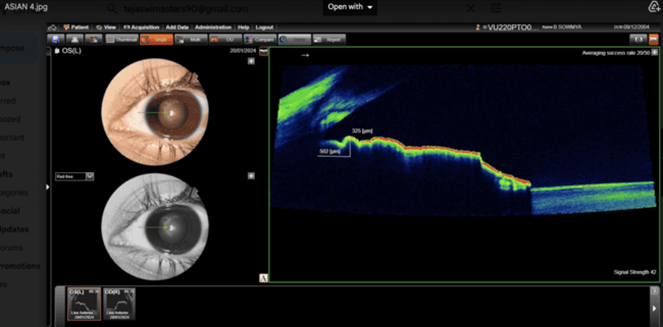

Volunteers Asians and Africans students selected from paramedical courses Gitam University, Visakhapatnam campus. In this analytical comparative  study, 400 eyes (100 Asians and 100 Africans), between the age of 18 to 35 years are selected for this study. Out  of 100 subjects  50 are males and 50 are females from Asian ethnicity and African ethnicity respectively. A comprehensive ophthalmic examination is carried out, includes Best Corrected visual acuity (BCVA) obtained after refractive correction, Anterior segment is evaluated by Slit lamp biomicroscopic examination, Fundus examination is carried out by + 78Ds lens,  Intra Ocular Pressure (IOP) recorded with Applanation tonometer. The cases with defective vision, IOP more than 21 mm of Hg, those who underwent LASIK, other Anterior segment diseases are excluded from this study. This study is conducted in the Department of Ophthalmology with the approval of Ethics committee of  Gitam Institute of Medical Sciences and Research, Visakhapatnam. All the cases are subjected to measurement of root of iris by the Optical coherent tomograph Topcon 3D OCT-1 Maestro 2 in static mode, 500 microns from the root of the iris. Nasal aspects of the root of the iris thickness of the Africans (Fig 1) and Asians are measured (Fig 2).

Fig 2: Fig: Iris thickness of Asian at T500 with 325 microns